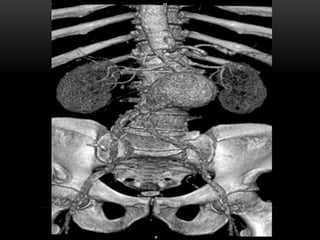

RECONSTRUCCIÓN DE VOLUMEN VR

• Toma todo el volumen de datos y suma la contribucion de cada voxel.

MAPAS DE COLOR

• Se asignan colores a los tejidos que se quieren visualizar.

• Asignan colores artificialmente .

RECONSTRUCCIÓN DE VOLUMENVR • Toma todo el volumen de datos y suma la contribucion de cada voxel.